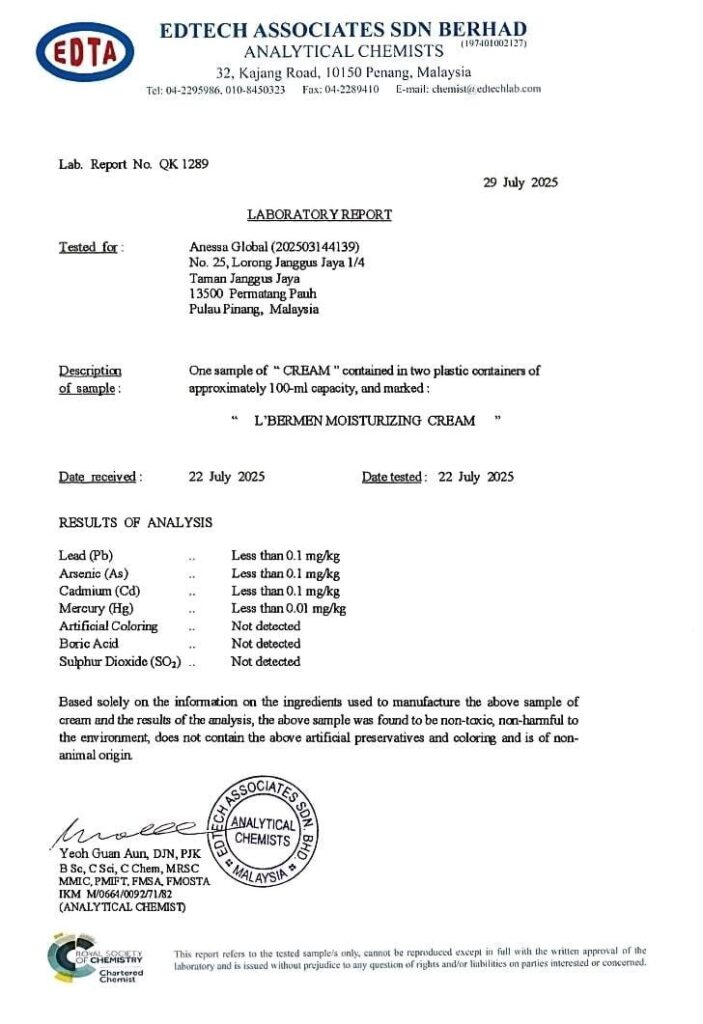

Krim yang Telah Disahkan TIADA Bahan Terlarang (Non-Toxic) & Lulus KKM

L’Bermen diformulasikan daripada esktrak tumbuhan & bahan botani. Tiada bahan terlarang dan telah disahkan oleh makmal